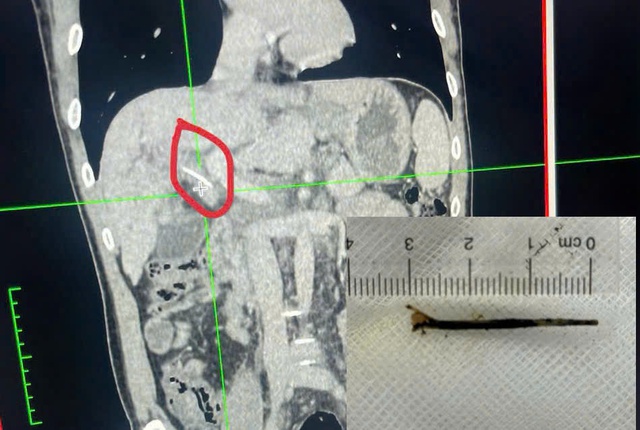

Ngày 26.3, theo thông tin từ Bệnh viện đa khoa Trung ương Cần Thơ, các bác sĩ Khoa Nội soi vừa nội soi mật tụy ngược dòng (ERCP) lấy xương cá dài khoảng 3 cm xuyên qua thành dạ dày vào đường mật của một bệnh nhân. Đây là ca hóc xương cá di chuyển rất hy hữu, biến chứng gây gián đoạn dòng chảy của mật, viêm đường mật, đau bụng kéo dài… thậm chí khiến bệnh nhân lo âu khi nghi ngờ bị ung thư.

Đoạn xương cá được lấy ra khỏi người bệnh nhân

Điều bất ngờ là hình ảnh CT - Scanner có cản quang ghi nhận bệnh nhân có một dị vật dài khoảng 3 cm nằm ở vùng rốn gan, nghi ngờ là nguyên nhân gây tắc mật.

Sau hội chẩn, ê kíp quyết định thực hiện kỹ thuật nội soi mật tụy ngược dòng (ERCP) để khảo sát và can thiệp lấy dị vật. Các bác sĩ đã phát hiện ống gan chung của bệnh nhân có xương cá đâm từ ngoài vào, phía trên tạo sỏi kẹt ngay xương. Ngay sau đó, các bác sĩ đã dùng kìm lấy dị vật là xương cá dài khoảng 3 cm thành công dưới hướng dẫn ống soi Spyglass; đồng thời đặt một stent vào nhánh gan phải giúp giải phóng tắc nghẽn đường mật. Sau 2 giờ thủ thuật bệnh nhân an toàn được chuyển Khoa Ngoại Tổng hợp theo dõi và điều trị. Hiện tại, bệnh nhân tỉnh táo, tiếp xúc tốt, tình trạng đau bụng cải thiện rõ rệt.